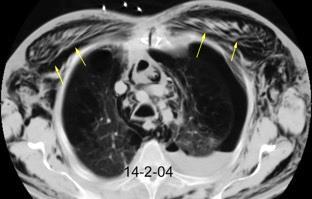

Masa axilar izquierda y derrame pleural derecho. Implantes pleurales, paraespinales . Ganglios en mamaria interna. Linfoma B difuso

Jaffe ES. Diagnosis and Classification of Lymphoma: Impact of Technical Advances.

2005. Masa pulmonar.

Linfoma NH de cél. B. Invasión Transtorácica.

Afectación axilar